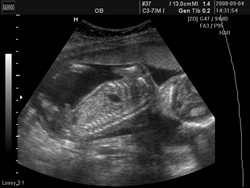

Halihó! :) Megjöttünk az Uh-ról, mutatok nektek képet:

Kristóffal minden rendben van, látszott a gerince, végtagjai (bár eddig is), a belső szerveivel is minden OK, magzatvíz is jó. :)

14 cm és 259 gramm. :))